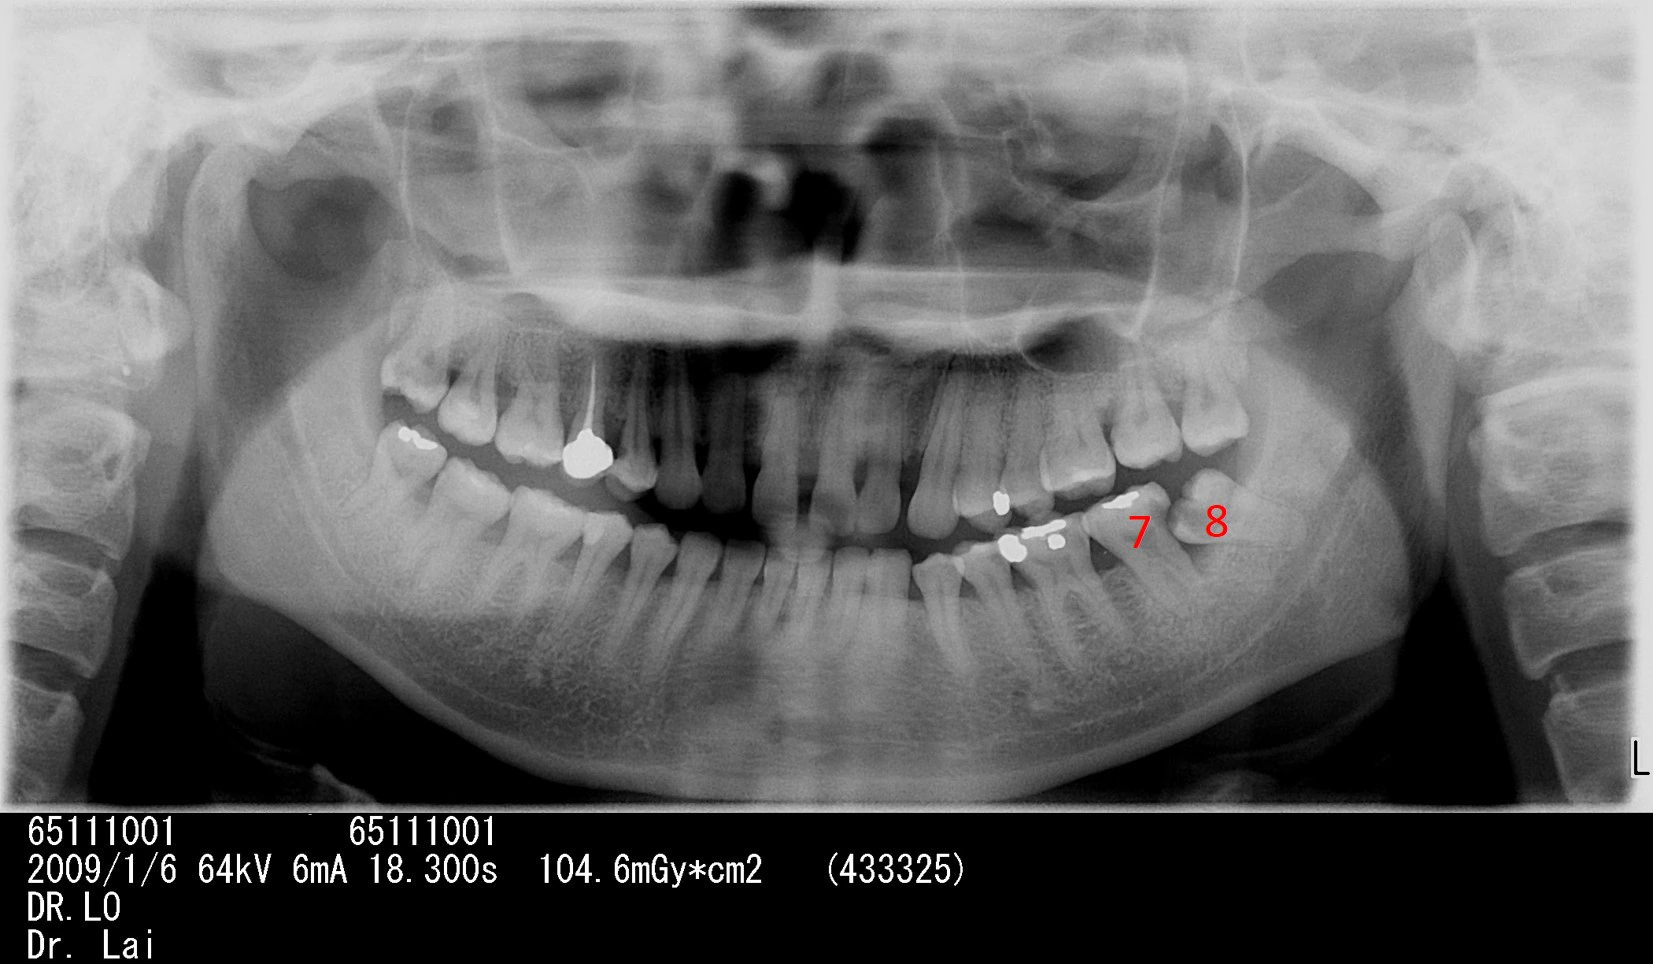

左下智齒不聽醫師建議拔除,5年後,智齒前面大牙也因智齒而蛀牙,最後拔除2顆大牙